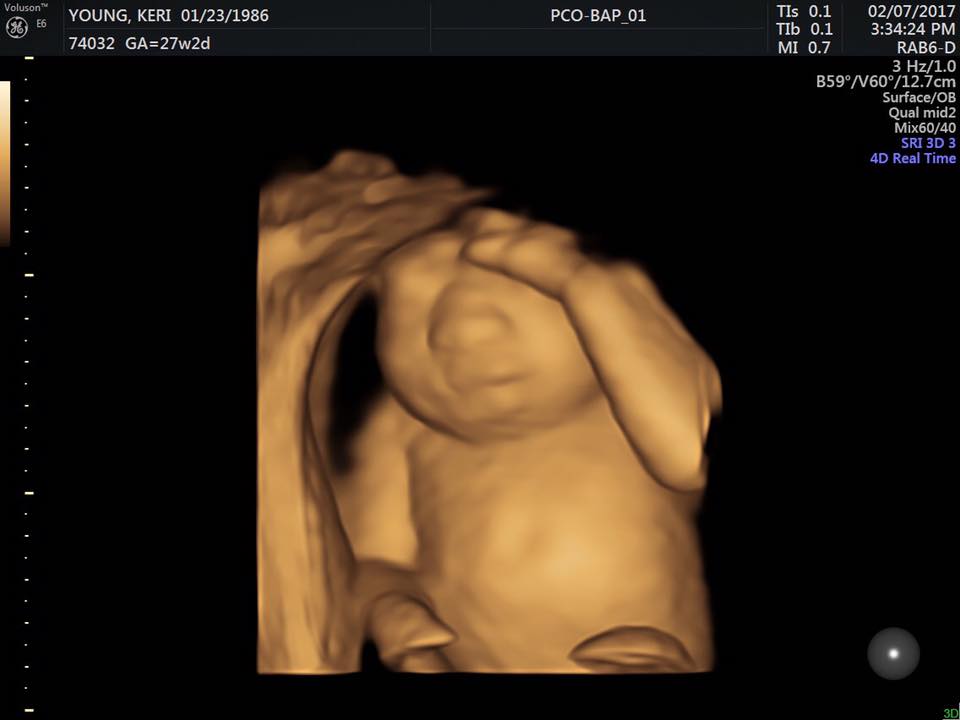

Nažalost, njihovu je obitelj zadesila neopisiva tuga u 19. tjednu Kerine trudnoće kada je otkriveno da djevojčica koju nosi ima anencefaliju, trajni defekt mozga zbog kojeg će umrijeti unutar nekoliko sati nakon rođenja. Odmah po saznanju strašne dijagnoze, odlučili su da će Keri ipak roditi djevojčicu i donirati njene zdrave organe.